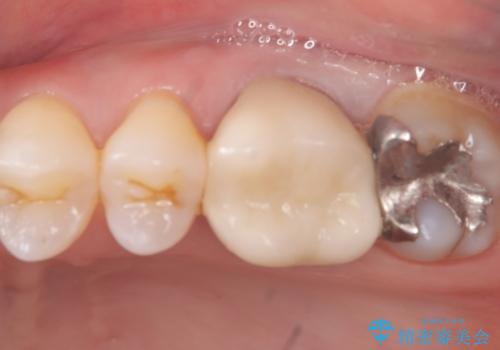

左上4近心に実質欠損を認め、遠心から咬合面にかけてはCR修復が施されていたため、MODインレー窩洞としました。

インレー接着操作時はラバーダム防湿を行っています。